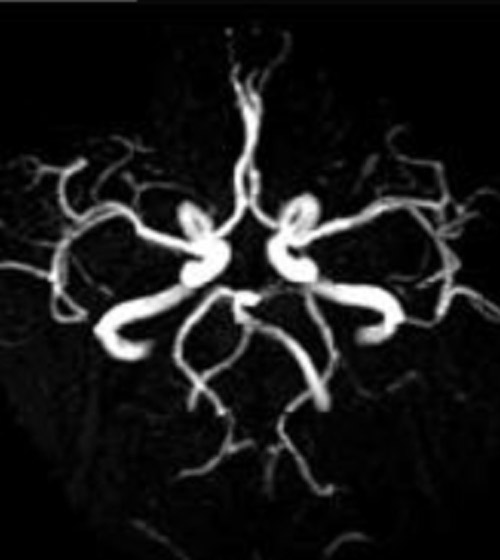

頭部MRA

脳血管の健康状態をチェックすることができ、脳動脈硬化の進み具合や血管内部が狭くなっているかなど調べることが可能です。